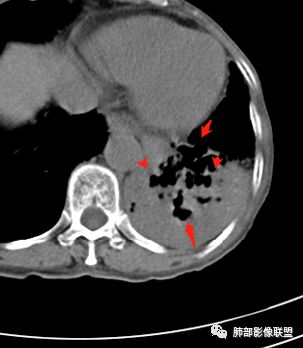

大家看看这支气管

这些支气管扩张

支气管扩张、扭曲成团,附近钙化灶

这例左下叶的体积是整体缩小的,左下叶的支气管主干稍微小一点点,然后左上叶的下舌段也有类似的病灶,然后我们看到一团乱的支气管扩张,但它有特点,边缘凹凸不平。那什么样的支气管扩张边缘会如此凹凸不平呢,等我截个图:

看最后一幅图,上面这个支气管,有可能是淋巴瘤,为什么?他的支气管稍扩张,直达远端、实变。

首先这幅图支气管很多地方是扭曲的,远端扩张的特别厉害。如果是肿瘤,首先考虑淋巴瘤,因为支气管可直达远端,稍扩张,但是它的前提是周围要实性占位的,而且它不会这样扭曲变形。我们看这个病例的支气管扩张,它支气管扩张占大部分区域,中间稍有些实性的结构,这就不符合了。这幅图你会发现所有支气管都是扩张的,实性部分偏少,外围胸水。所以我更倾向慢性炎性病变,能够引起支气管扩张的炎性病变有哪些?结核?NTM?支扩伴感染?大方向是慢性炎性病变。这些左下肺播散出来的病灶,咳中等量黄浓痰,我考虑还可能合并细菌感染。